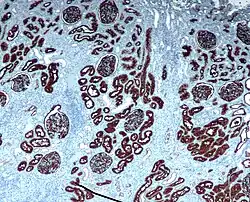

Immuunhistochemie, ook wel immunohistochemie[1] of IHC, is de techniek waarmee men specifieke eiwitten in een weefselcoupe kan aantonen met behulp van (fluorescent) gelabelde antilichamen.[2] De naam is samengesteld uit immunis, wat verwijst naar de gebruikte antilichamen, en histos dat weefsel betekent.

Immuunhistochemie wordt onder meer gebruikt in de pathologie en diagnostiek, onder meer bij het vaststellen van abnormale cellen, zoals die in tumoren. Men zoekt naar moleculaire markers die kenmerkend zijn voor bepaalde cellulaire processen, zoals proliferatie of geprogrammeerde celdood (apoptose). IHC wordt gebruikt om de distributie en lokalisatie van eiwitten in verschillende delen van biologisch weefsel te bestuderen.

De indirecte methode gebruikt een ongelabeld primair antilichaam (eerste laag) dat reageert met het weefselantigeen, en een gelabeld secundair antilichaam (tweede laag), dat reageert met het primaire antilichaam. Het secundaire antilichaam moet gevormd zijn tegen het antilichaam van de diersoort dat het primaire antilichaam heeft gevormd. Deze methode is gevoeliger dan de directe methode door de versterking van het signaal doordat de primaire antilichamen meerder bindingsplaatsen heeft voor het secundaire antilichaam. De tweede laag kan gelabeld zijn met een fluorescerende stof of een enzym. Een veel gebruikte methode koppelt een biotinyleerd secundair antilichaam met streptavidine-horseradish peroxidase. Dit reageert met 3,3'-diaminobenzidine (DAB) dat een bruine kleuring geeft op plaatsen waar de primaire en secundaire antilichamen binden. Deze methode wordt de DAB-kleuring genoemd. Door gebruik te maken van nikkel kan de reactie versterkt worden doordat er een dieppaarse/grijze kleur gevormd wordt.

IHC heeft het grote voordeel dat het mogelijk is om precies aan te geven waar een bepaalde component zit binnen het onderzochte weefsel. Daarnaast is IHC een effectieve methode om weefsels te onderzoeken. In de neurologie wordt hiervan gebruikgemaakt om het voorkomen van bepaalde proteïnes in bepaalde delen van de hersenen. Een groot nadeel is dat, in tegenstelling tot immunoblotting waarbij de kleuring wordt gecontroleerd aan de hand van het moleculair gewicht, dat het onmogelijk is om te bewijzen dat de kleuring overeenkomt met het gezochte proteïne. Daarom moeten primaire antilichamen worden gevalideerd door een procedure zoals Western blot. De techniek wordt nog meer gebruikt in de diagnostische chirurgische pathologie voor het typeren van tumoren (bijvoorbeeld immunokleuring van e-cadherine om te differentiëren tussen het positief-kleurende ductaal carcinoma in situ (DCIS) en het negatief-kleurende lobulaire carcinoma in situ (LCIS)[3]).